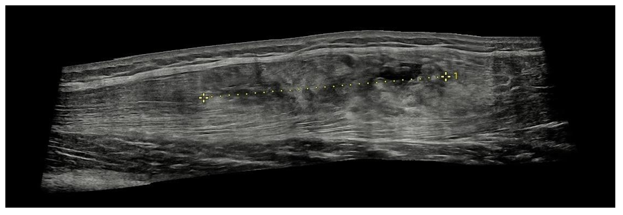

Ultrasound imaging revealed an intramuscular fluid collection and partial separation of the muscle fibers within the rectus femoris, consistent with an intramuscular degloving lesion (Figure 1&2).

Figure 2 Panoramic longitudinal ultrasound image of rectus femoris muscle

Measure identified with number 1: 7.48 centimeters.

Though less specific, ultrasound offers useful initial assessment: hypoechoic fluid collection, subtle fiber separation, and altered echotexture in the inner muscle portion may be visible, especially with high-frequency probes. In our case, ultrasound revealed the fluid plane and fascial separation, consistent with IDI. However, its sensitivity for quantifying retraction or distinguishing subtle separation is limited. Thus, MRI remains essential for comprehensive evaluation and prognostication.2,4